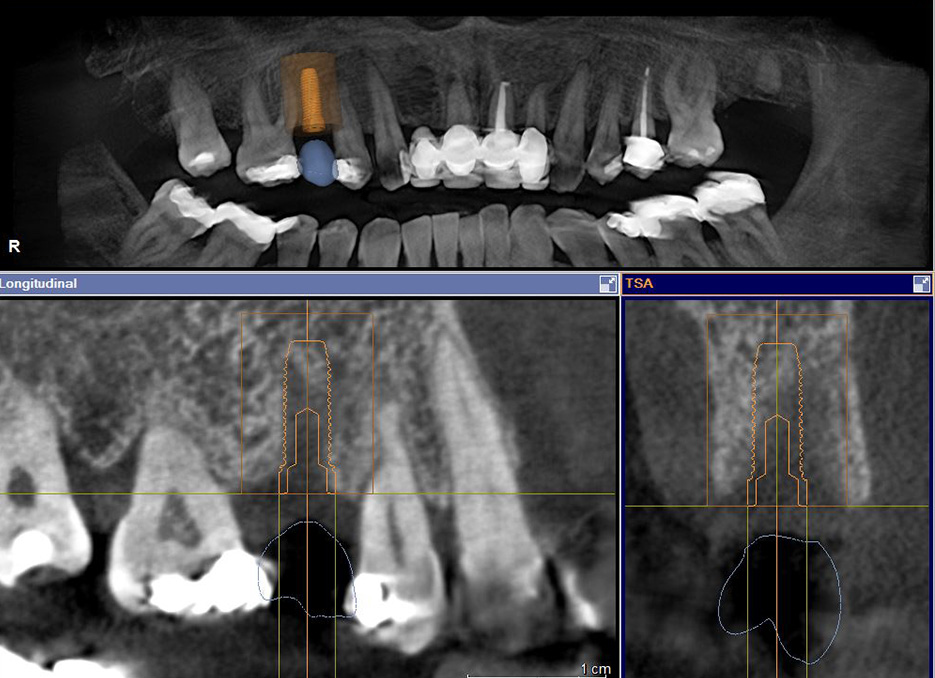

3D-Röntgen (DVT)

Import der CEREC-Planung in das 3D-Röntgenbild und Planung der exakten Implantatposition